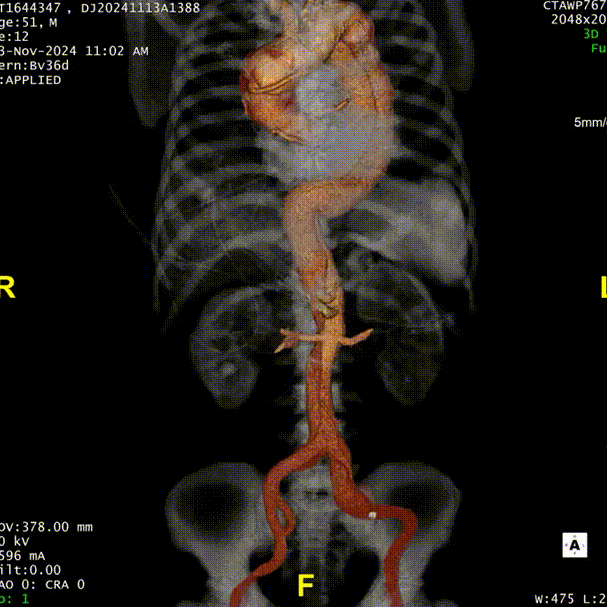

患者入院后行CTA检查,CTA提示患者为A型主动脉夹层。弓上三根分支血管及内脏区分支血管均发自真腔,夹层远端累及至髂总动脉。

术前CTA.

术前3D重建